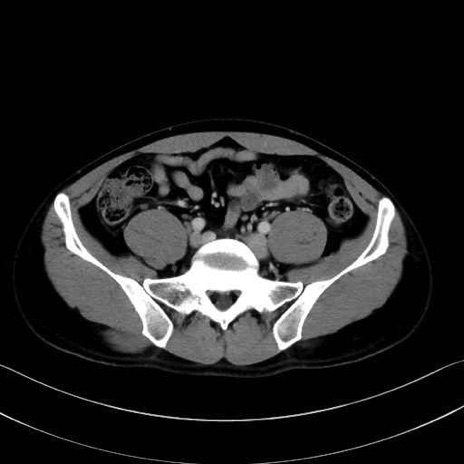

2. 腸腰筋群と骨盤底筋

腸骨筋 (Iliacus)

3. 殿部の筋肉(表層・中層・深層)

大殿筋 (Gluteus maximus)

中殿筋 (Gluteus medius)

小殿筋 (Gluteus minimus)

大腿筋膜張筋 (Tensor fasciae latae)